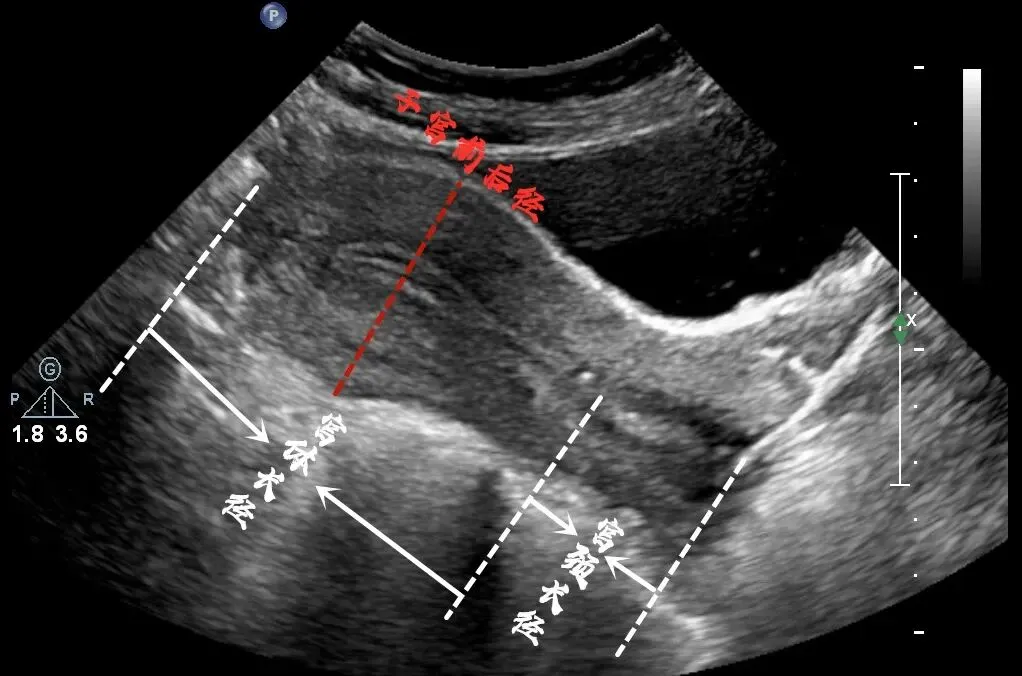

经腹耻骨联合上横切

取仰卧位,将探头横置于耻骨联合上 缘,探头的前端对应人体的右侧,声束指向腹后方。

●子宫横径的测量

★测量标准切面:取近子宫底部的横切面显示宫腔线最宽处

★测量方法:沿两侧宫角处稍下方测量宫体两侧的最大横径